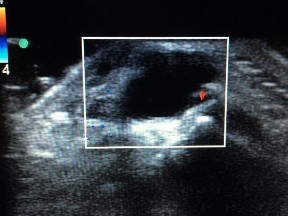

Figure 1 is the ultrasound of a 23-year-old patient who has had a volar radial 1.5-cm tender and painful wrist mass for 6 months. The additional workup prior to surgery should consist of